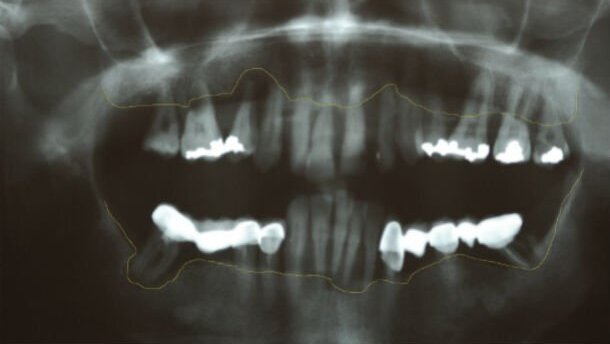

All’esame obiettivo e radiografico si evidenzia uno stato di avanzata malattia parodontale con severa compromissione degli elementi 11-12-13-14-16-17-21-22-23 e 48-43-42-41-31-32-33-38, e una importante perdita di osso alveolare del gruppo frontale superiore ed inferiore causa estrusione dentale.

Lo skyline dell’osso residuo tracciato sulla OPT risulta estremamente irregolare e lascia immaginare importanti difetti intraossei che verranno confermati dal sondaggio parodontale e da una indagine Tc successiva (Fig. 1).